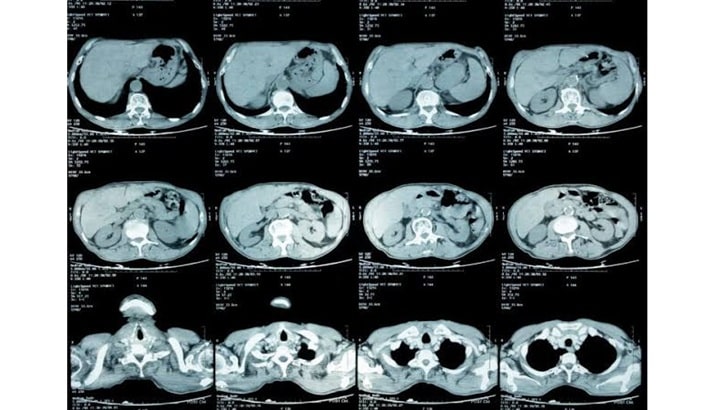

سی تی اسکن شکم یکی از دقیقترین روشهای تصویربرداری پزشکی است؛ این روش به کمک اشعه ایکس و فناوری پیشرفته، تصویرهای مقطعی بسیار واضحی از اندامهای داخلی شکم به دست میدهد. این روش، در تشخیص بیماریهای گوارشی، کلیوی، کبدی و حتی برخی تومورها نقشی بسیار مؤثر دارد.

نقش سی تی اسکن شکم در ارزیابی کبد، طحال و پانکراس

اندامهای حیاتی مانند کبد و طحال، معمولاً تا زمان بروز علائم شدید، تغییرات داخلی خود را نشان نمیدهند. در چنین شرایطی، سی تی اسکن شکم کمک بزرگی به تشخیص زودهنگام میکند.

تشخیص تومور و کیستهای کبدی

سی تی اسکن شکم میتواند وجود تودههای خوشخیم یا بدخیم در بافت کبد را با دقت بالا نشان دهد. در مرکز تابا، پزشکان از سی تی اسکن شکم و لگن بدون تزریق برای ارزیابی دقیق شکل، اندازه و محل ضایعات استفاده میکنند.

بررسی عملکرد طحال و التهاب پانکراس

اختلال در عملکرد طحال یا پانکراس میتواند باعث درد یا ورم در قسمت فوقانی شکم شود. در چنین مواردی، سی تی اسکن شکم و لگن به تشخیص التهاب پانکراس (پانکراتیت) و بررسی اندازه طبیعی طحال کمک میکند.